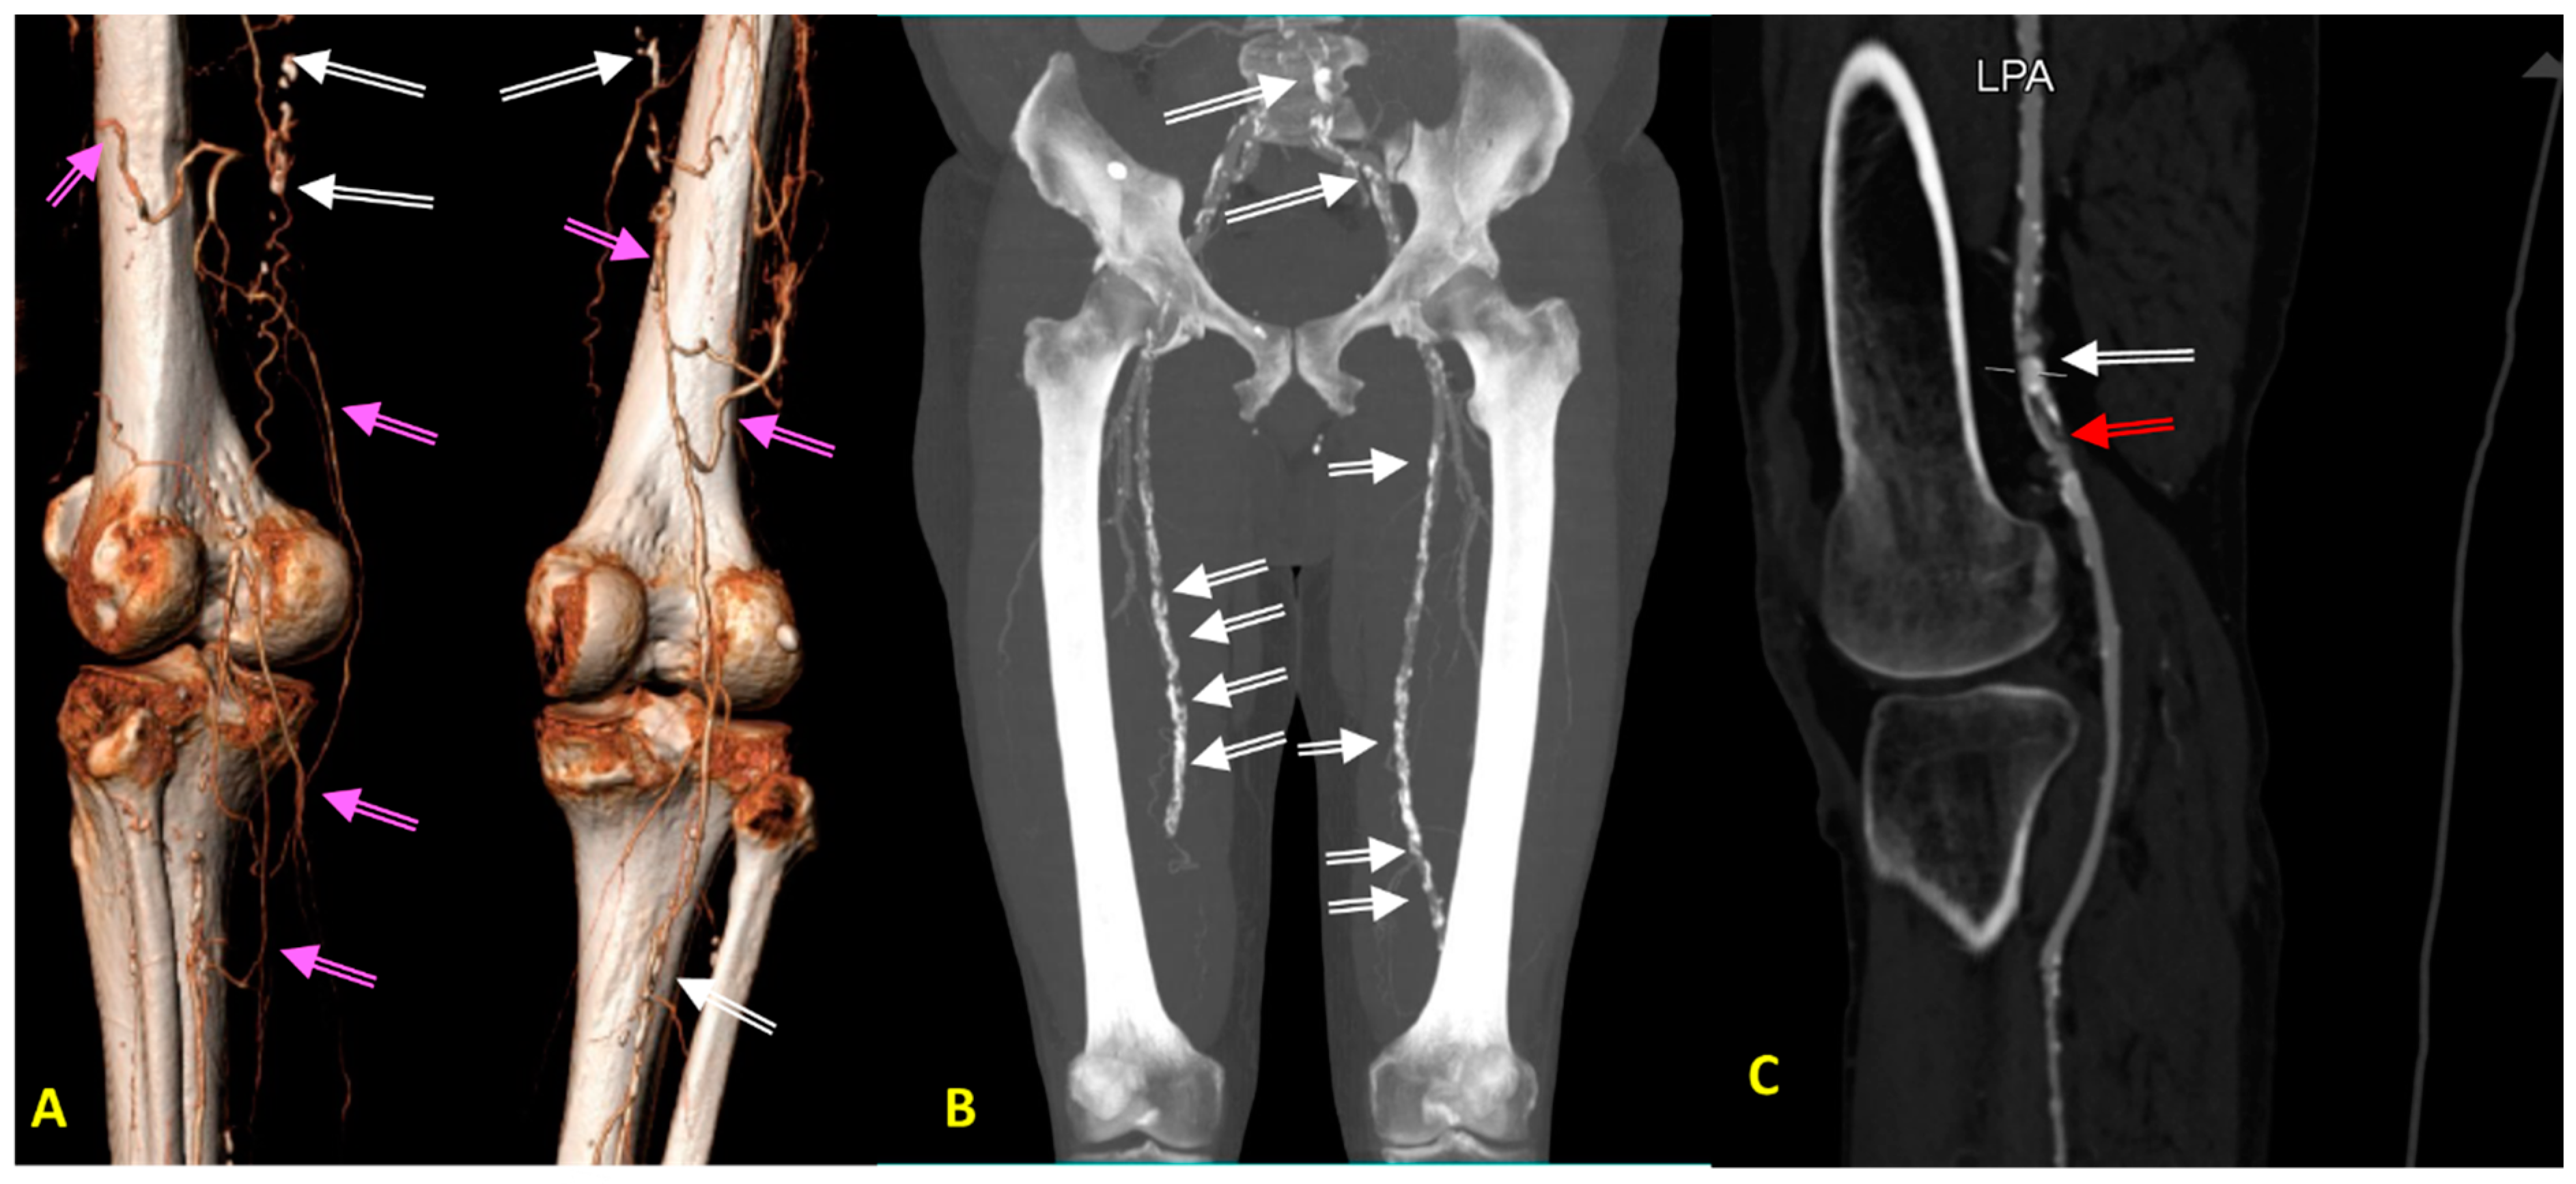

| Diversities in the elderly patients | Severely calcified atherosclerotic lesions; stenosis in more than one carotid/vertebral artery; excessively elongated vessels, often with loop formation or acute angles <90%; high arterial stiffness and raised vascular resistance; atherosclerotic lesions in intracranial segments and cerebral arteries. | Diffuse, multilevel atherosclerotic lesions, also involving the tibiofemoral trunk and arteries below the knee; development of collateral circulation. In diabetics, superimposed lesions of diabetic angiopathy and peripheral neuropathy, hyalinization of the endothelium, ulcerations, trophic changes, reddening of the toes, and gangrene. | Stable atherosclerotic lesions, with a similar degree of progression and lumen reduction to those before age 70, but less prone to rupture and thrombosis. More fibrous components and calcification in plaques, fewer inflammatory cells and lower lipid composition, regression of necrotic and lipid core, better developed peripheral circulation. | Active atherosclerotic lesions, often coexisting with advanced atherosclerotic lesions in the coronary, carotid/vertebral arteries; abdominal aortic aneurysm and Leriche syndrome. | |

| Methods of diagnosing atherosclerotic lesions in older people | Preferred | Doppler-duplex ultrasound—good resolution, no need for a contrast agent. Limitation—calcifications causing an acoustic shadow make it difficult to assess the vessel lumen. CT and MRI of the brain—diagnosis of ischemic lesions. | Doppler-duplex ultrasound—good resolution, no need for a contrast agent. Limitation—calcifications giving an acoustic shadow make it difficult to assess the vessel lumen. ABI indicates lower limb atherosclerosis when it is <0.9, but it is often nondiagnostic in people with diabetes due to intimal calcifications (ABI > 1.4). TBI in patients with diabetes and non-diagnostic ABI (>1.4); TBI < 0.7 is diagnostic for PAD. Pulse oximetry—measurement of blood pressure on the toe—a prognostic indicator of ulcer healing. | Treadmill test—assessment of exercise tolerance and detection of new ischemic changes. Echocardiography—assessment of left ventricular systolic function; wall motion abnormalities; diastolic function; exclusion of intracardiac problems such as thrombus, valve disease, pericardial effusion, features of pulmonary embolism. SPECT—assessment of viability and ischemic area on isotope. | Doppler-duplex ultrasound—good resolution, no need for a contrast agent. Limitation—obesity makes the examination difficult/impossible. |

| Limited | CTA—anatomical assessment, but test affects renal and thyroid function, caution if renal failure with eGFR below 50 mL/min/kg, calcifications make assessment of vascular stenosis difficult. MRA—anatomical assessment, possible assessment of plaque morphology, but long examination, requires administration of gadolinium (caution if eGFR < 30 mL/min); claustrophobia. | CTA—anatomical assessment, but test affects renal and thyroid function; caution if renal failure with eGFR below 50 mL/min/kg, calcifications make assessment of vascular stenosis difficult. MRA—anatomical assessment; possible assessment of plaque morphology, but long examination, requires administration of gadolinium (caution if eGFR < 30 mL/min); claustrophobia. | CTA—anatomical assessment, but test affects renal and thyroid function; caution if renal failure with eGFR below 50 mL/min/kg; calcifications make assessment of vascular stenosis difficult. MRA—anatomical assessment; possible assessment of plaque morphology, but long examination, requires administration of gadolinium (caution if eGFR < 30 mL/min); claustrophobia. | CTA offers anatomical assessment, but it affects renal and thyroid function; caution if renal failure with eGFR below 50 mL/min/kg; calcifications make assessment of vascular stenosis difficult. MRA—anatomical assessment; possible assessment of plaque morphology, but long examination, requires administration of gadolinium (caution if eGFR < 30 mL/min); claustrophobia. Scintigraphy with captopril test—not recommended for diagnosis of RAS (class III recommendation). Renal vein renin activity assessment—not recommended (class III recommendations). | |